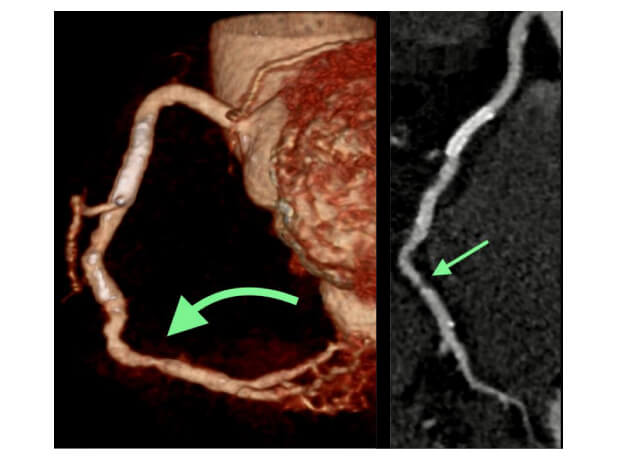

Stent of the intermediate segment and stenosis of the distal segment of the Right Coronary Artery

Coronary CT Angiography shows patent stent of the intermediate segment and high grade stenosis of the distal segment of the Right Coronary Artery.